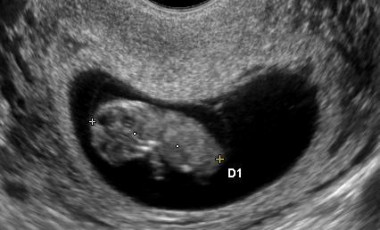

Önmagában már az is felháborodást keltett, hogy a rendelet-módosítás társadalmi egyeztetés nélkül született, de a Belügyminisztérium az egészségügyi dolgozókat sem tájékoztatta. „Olyan helyzetbe kerültünk, amihez nem kaptunk segítséget” - mondta Dr. Wafa Diána szülész-nőgyógyász, és hozzátette, hogy noha az új rendelet szívhang-törvényként híresült el, életjeleket másképp is be lehet mutatni. „Ezt a helyzetet többen többféleképpen kezeljük. Én megkérdezem a pácienseket, hogy szeretnék-e látni az életjelenségeket, és ha azt mondják, hogy nem, akkor nem kényszeríthetem rájuk. Sok kolléga hasonlóan gondolkodik. Köt minket a jogszabály, elvileg be kell mutatnunk az életjeleket, de ha valaki elfordul és nem néz oda, akkor mit tudunk mi tenni a rendelőben?” Dr. Wafa Diána Mérő Verához hasonlóan dühös, mert úgy érzi belekényszerítették a helyzetbe, miközben az egészségügyi rendszernek jelentős szerepe van abban, hogyan élik meg a nők az abortuszt. „Mi vagyunk a végrehajtók, mi szívjuk ki az embriókat. Próbálom nem elfojtani magamban az érzéseket ezzel kapcsolatban. Arra jutottam, hogy mindenkinek joga van a méltó élethez. Így próbálom feldolgozni a helyzetet.”